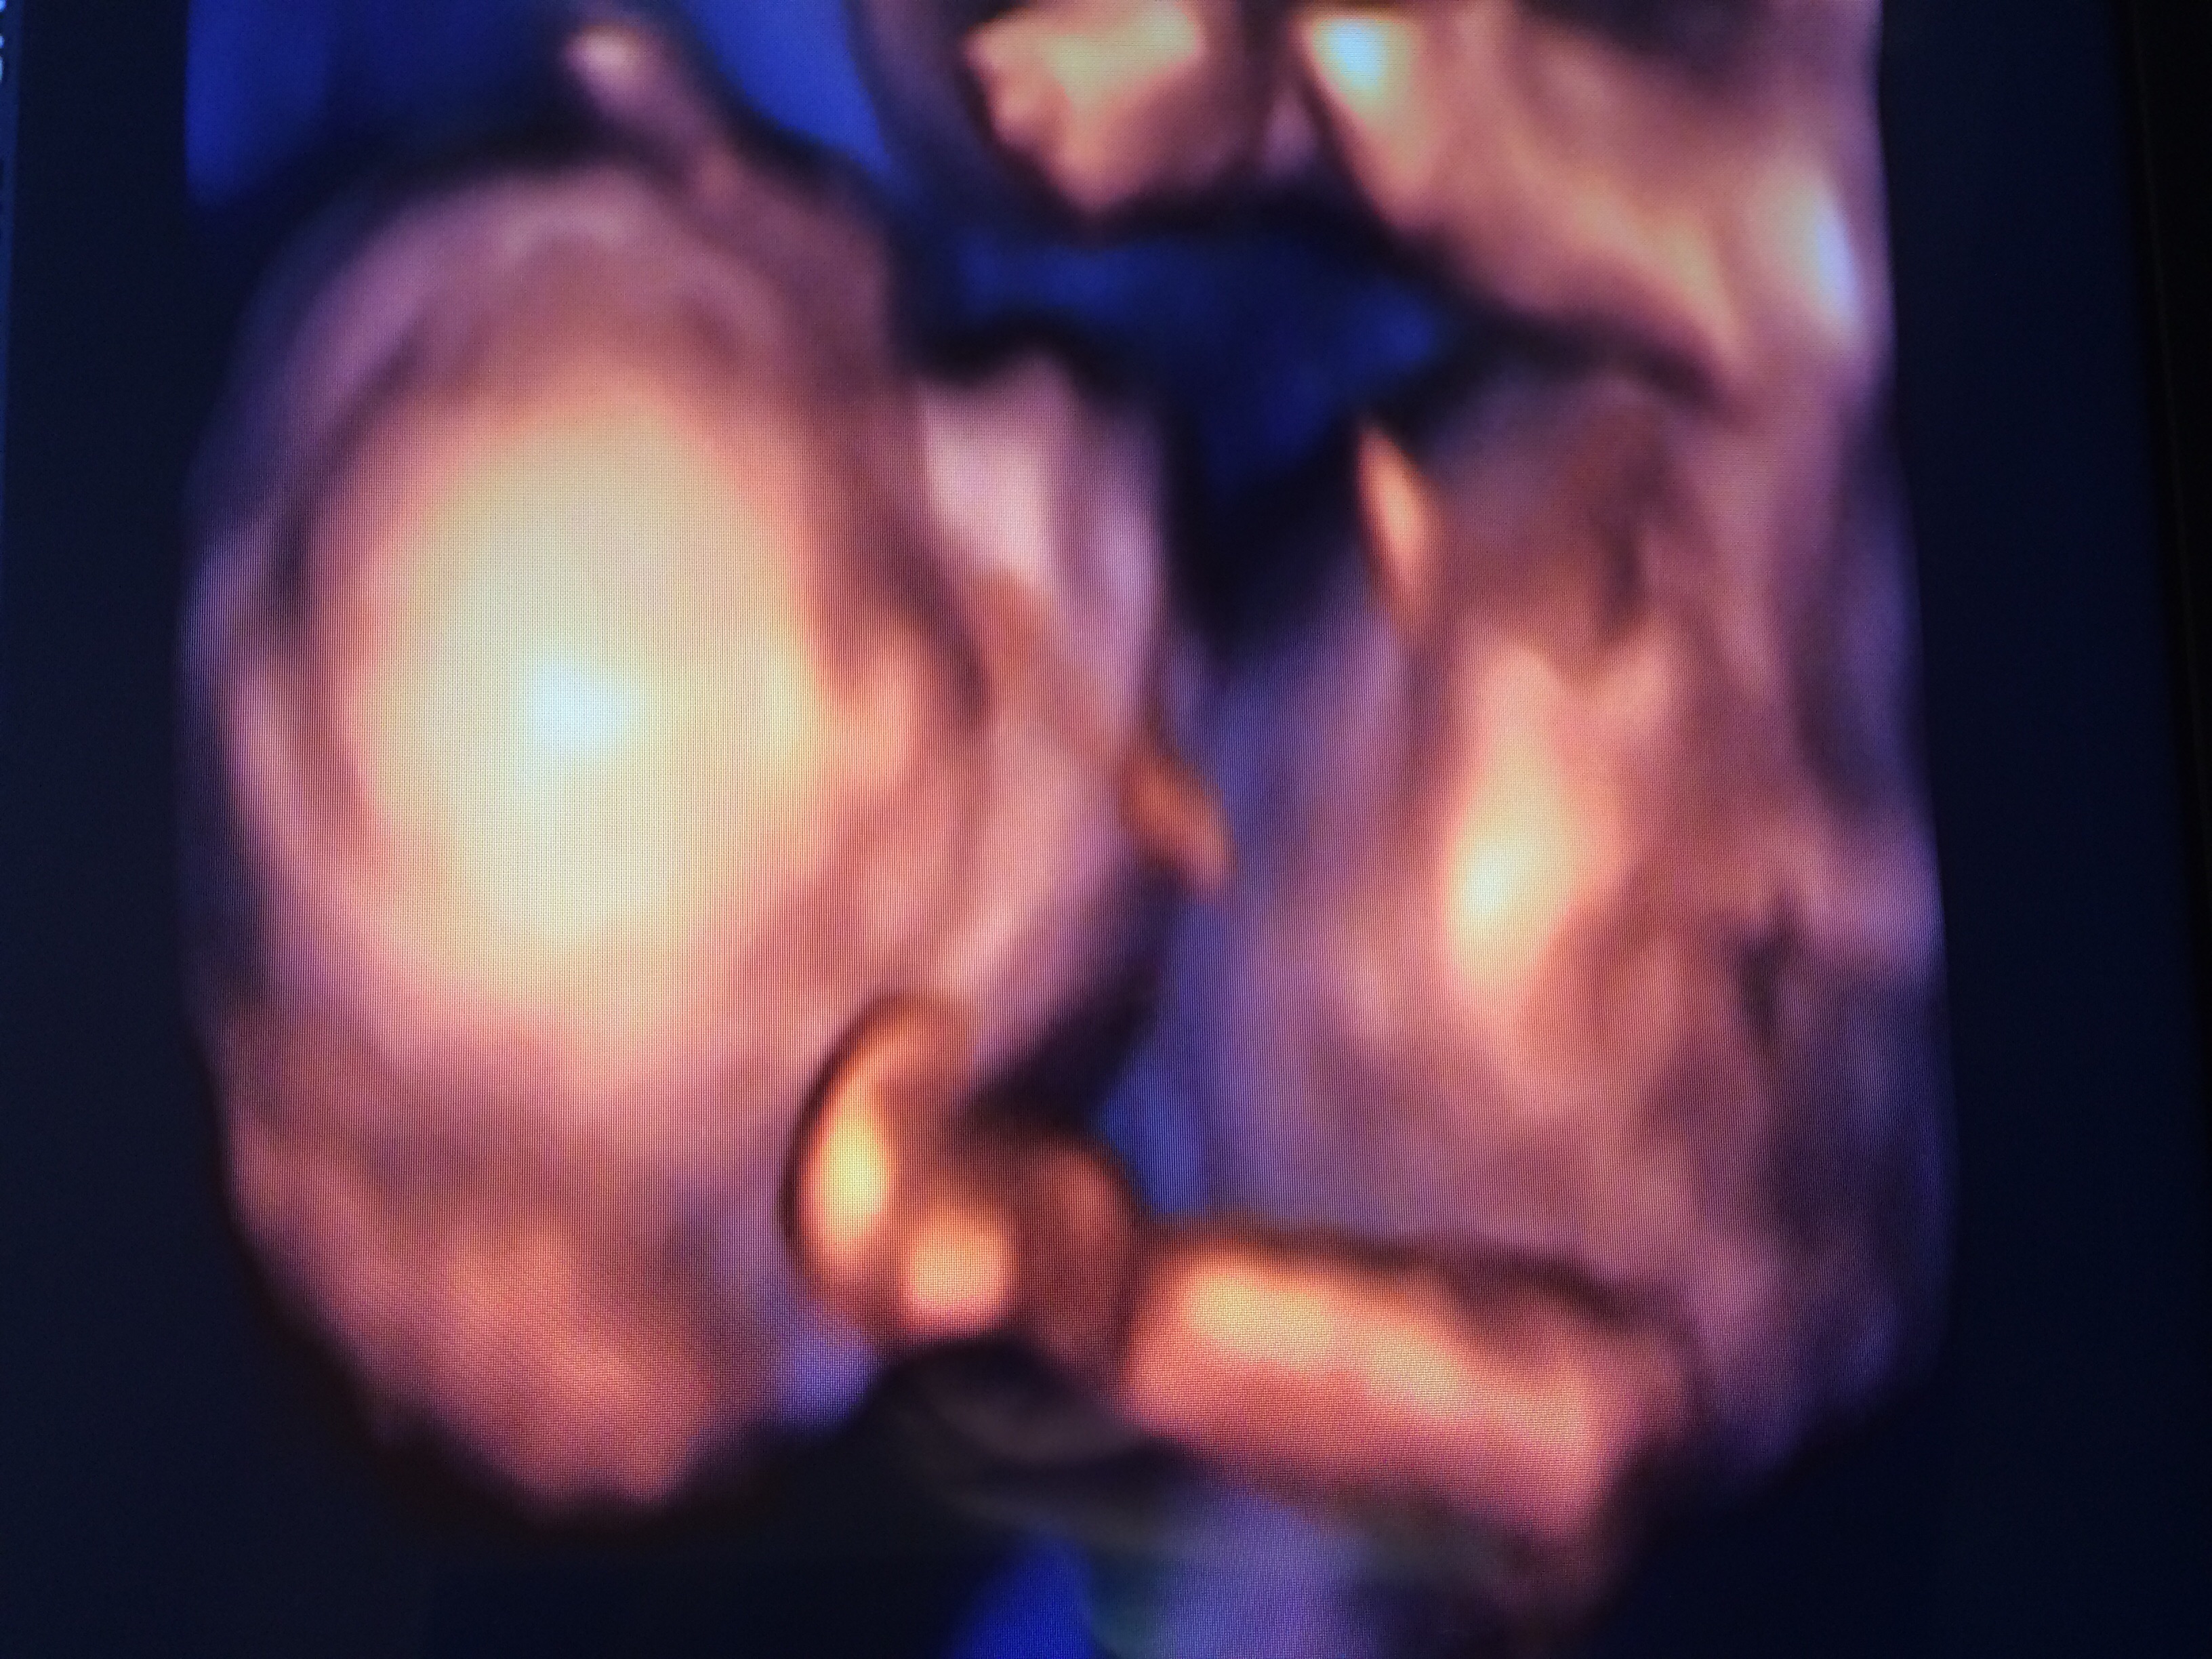

Had our ultrasound yesterday and we are adding another healthy little boy (no question about it) to our family. That will give us boy-girl-boy. The boys have us outnumbered but they will be our protectors. Due the 11th but usually go late. Go team blue!!

It's a BOY!!!! His 2 big sisters can't wait to meet him. He was active, healthy, but a bit small, so he is now due on New Years Day. We could not be happier!!!

I'm officially on TEAM BLUE!!